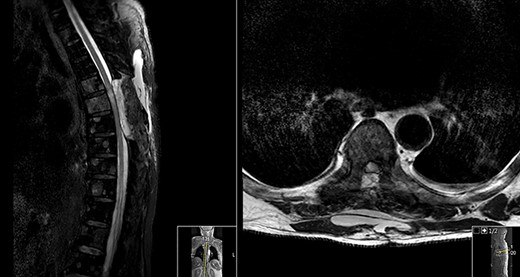

Postoperative MRI (Fig. 2) revealed a de novo T2 hyperintensity, possibly due to retraction of the thecal sac during surgery and consequently spinal cord lesion.

No hydrosyringomyelia or other complications were visible.